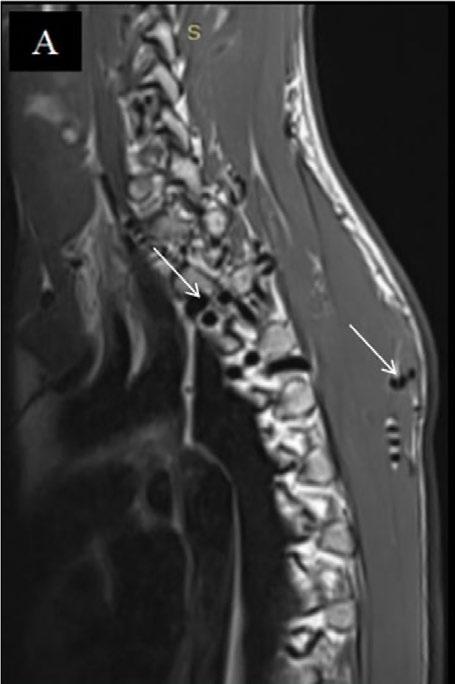

Create a flipbook